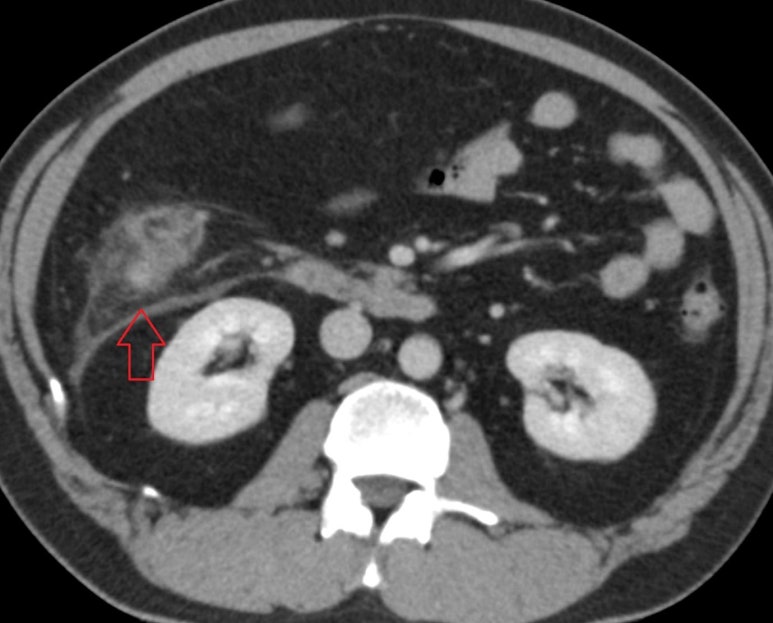

게실염, 충수염, 하복부통증 증상의 원인을 정확하고 신속하게 진단합니다.